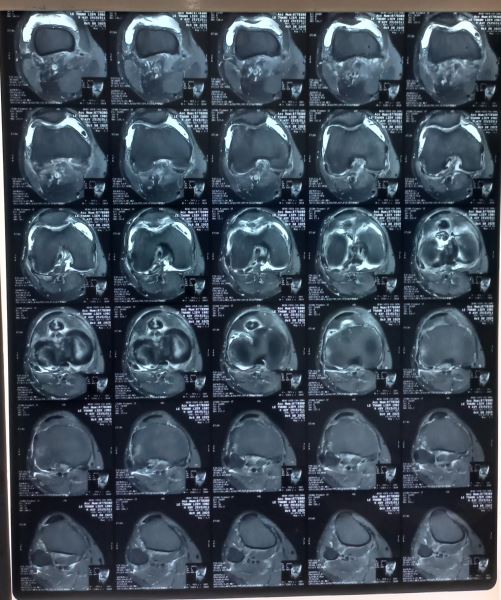

Chúng tôi nghĩ đến bệnh Synovial Osteochondromatosis một loại bệnh hiếm gặp và cho bệnh chân chụp MRI khớp cho kết quả sau: